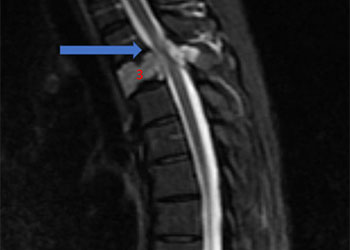

Based on the MRI findings and the clinical presentation, a spinal dural fistula was presumptively diagnosed and a spinal angiogram recommended with planned attempt to embolize a fistula if encountered. Spinal angiography confirmed a spinal dural fistula fed from radiculomedullary branches off the left T6 pedicle and draining into a spinal vein (Figure 2B & 2D).

No spinal arteries were identified from this pedicle and after provocative testing with lidocaine and amytol injection confirmed that no arterial input to the spinal cord, the fistula was sealed with one injection of onyx glue (Figure 2C). Post-embolization angiogram confirmed no residual filling of the fistula (Figure 2D).

Pre-Treatment (Figure 2A and 2D), At Treatment (Figure 2B – Onyx Glue Cast), and PostTreatment (Figure 2C)